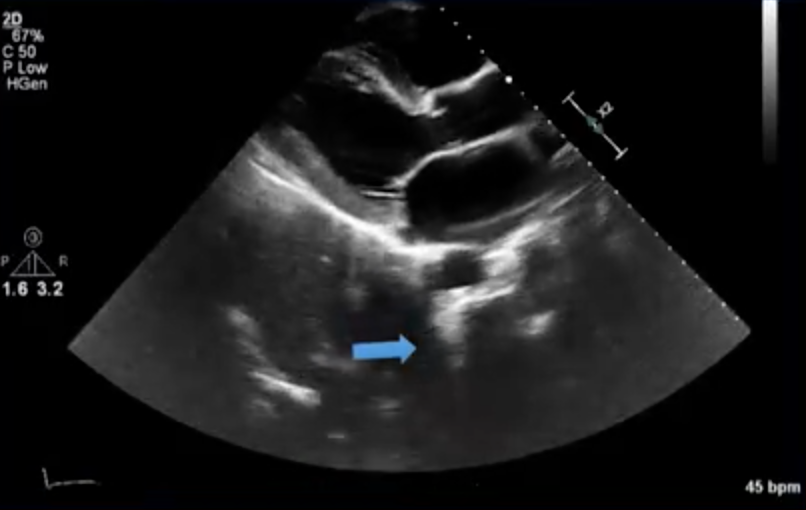

The Type of Artifact Shown Here….

Bright coumadin ridge on TEE with Hazy Structure that could be mistaken for a thrombus but is actually reverbertion of the bright LAA/coumadin ridge